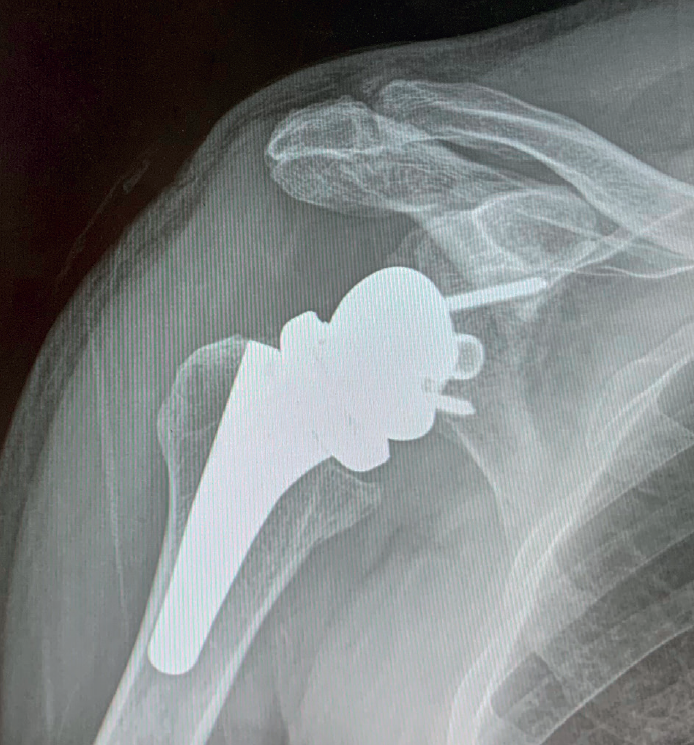

A more controversial issue is its indication in patients with massive cuff rupture in the absence of arthropathy, since it implies performing joint replacement of a joint without osteoarthrosis. In these cases, reverse shoulder replacement has been shown to be an effective alternative that affords predictable pain relief and improved function(15,17)(Figures 1 to 5).

Reverse shoulder replacement shifts the center of rotation distal and medial (Figure 5), increasing the lever arm of the deltoid muscle and recruiting more anterior and posterior fibers of the muscle, improving its function in patients without rotator cuff(1,19,20). In general, the patients can be expected to show increased anterior flexion and abduction of the shoulder. Having greater or lesser external rotation will depend on the quality of the teres minor and infraspinatus, among other factors (Figure 4). With regard to internal rotation in patients with reverse shoulder replacement after massive rupture, the results are less predictable and are conditioned by the implant design and the characteristics of the patient, among other factors. We must know the functional limitations of the implant and inform our patients about the results that can be expected.